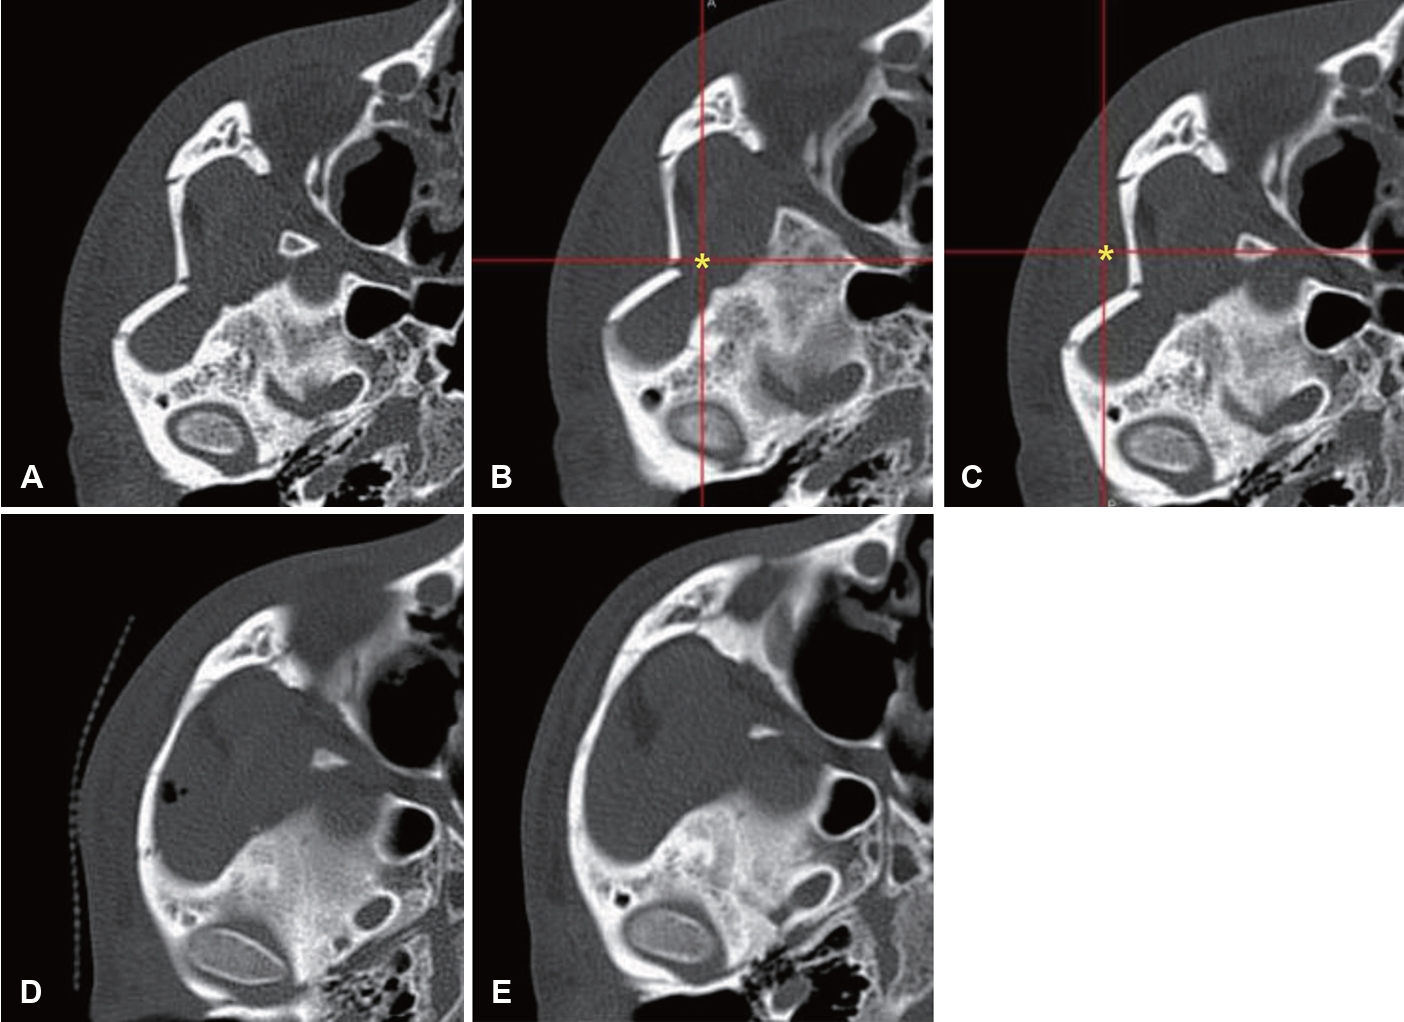

모든 환자는 외상 후 평균 8.12일, 최저 1일에서 최고 34일에 수술을 받았으며, 수술 시간은 평균 43.6분이었다. 수술은 영상유도수술 시스템을 접목한 Gillies 접근법으로 시행되었으며, 모든 증례에서 정복 기구의 삽입 위치 및 골절편의 정복 상태를 수술 중에 실시간으로 확인하였다(Fig. 2).

Fig. 2.Representative case. A: Preoperative axial CT. B: Intraoperatively, the navigation pointer is indicating the most depressed area (asterisk) of the zygomatic arch. C: Intraoperatively, the navigation pointer is indicating the position of the reduced zygomatic arch (asterisk) after reduction. D: Immediate postoperative axial CT. E: Postoperative 3-month axial CT with good alignment. Table 1.Characteristic of patients REFERENCES1. Cohn JE, Othman S, Bosco S, Shokri T, Evarts M, Papajohn P, et al. Management of isolated zygomatic arch fractures and a review of external fixation techniques. Craniomaxillofac Trauma Reconstr 2020;13(1):38-44.